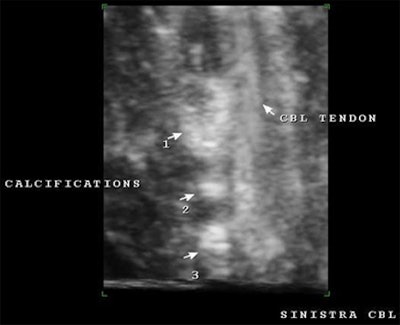

| 3D reconstruction with surface rendering of the long head of the biceps tendon with three macrocalcifications seen to the left side of the untorn tendon in a patient with tendinitis. |